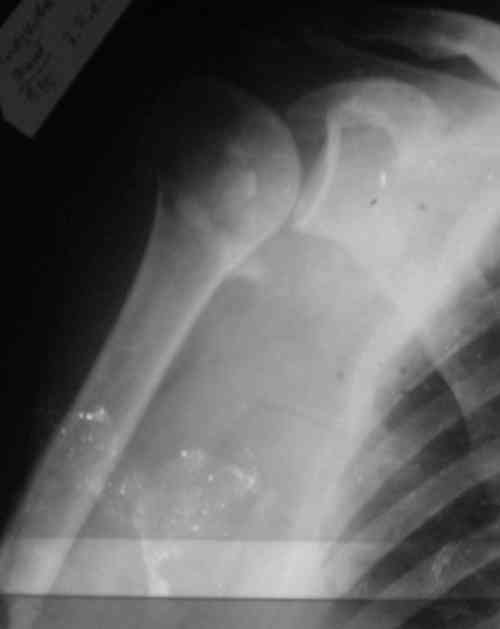

Судя по Р-граммам имеется оскольчатый перелом головки плеча. Во время открытой репозиции имеется большой риск "развалить" перелом, что значительно ухудшит кровоснабжения отломков. А так, на мой взгляд контакт м\у отломками достаточный, не смотря на наличие ротационного смещения головки думаю лучше продолжать консерватикное лечение. С уважением.

Судя по снимкам еще имеется перелом головки плеча, и чрезкостный отрыв вращательной манжеты. Для уточнения характера перелома не иешало бы сделать КТ. Если вести консервативно, то после сращения перелома будет ограничение движений в суставе не устраивающее больную. Я склоняюсь к оперативному лечению( накостный остеосинтез Т- Г образная пластина, лучше LCP для проксимальног плеча, обязательно подшить на место манжету).

В соответствии с работами Neer данный перелом можно классифицировать как однофрагментарный, так как нет диастаза более 1 см и углового смещения более 45 градусов - такие переломы лечатся консервативно. Рентген контроль каждые 10 дней- если смещение не увеличивается, то через 3-4 недели разработка движений в суставе

Уважаемый Сергей! Вы правильно написали критерии, но недооценили степень смещения в переломе хирургической шейки. Посмотрите ещё раз, это Two part fracture.

Ув. коллеги. С удовольствием выслушал ваши предложения но все равно сделал по-своему. Под проводниковой анестезией произвел попытку закрытой репозиции на 10-е сутки, вроде бы неплохо получилось. Кроме того, фрагменты головки имеют конткат между собой, главное, они сохраняют васкуляризацию. при остеосинтезе я думаю не обошлось бы без извлечения головки, сбора вне сустава и обратному инвертированию. Есть риск аваскулярного некроза. Фрагменты головвки настолько малы, и думаю тоже расколоты - куда совать металл? Благодарю за дискуссию. Снимки завтра скину.

Снимки на 1-е сутки после репозиции и на 8- сутки после репозиции.